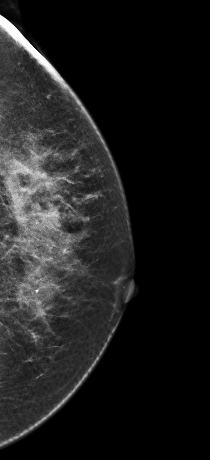

V-preview图像:

影像描述: 在2D常规图像上并没有发现明显异常,只是感觉左乳外上象限局部不对称腺体结构有些乱,可见散在颗粒样钙化,在V-Preview(合成2D)也没有发现明显异常改变,但在3D-plane图像上我们可以明确左乳外上象限局部腺体结构紊乱,内见多颗钙化(由于医院才刚刚开展这项新技术检查医生在诊断阅片上经验不足及固有的2D阅片模式忽略了动态连续观察病灶,最后诊断为良性病变),3D动态连续薄层放大观察钙化灶我们会发现病变区钙化灶呈多形性,串珠样排列,并不是2D 和V-Preview显示的颗粒样良性钙化表现 影像诊断: 左乳外上不对称致密,考虑良性病变,BI-RADS 2级 病例点评: 病理证实:左乳导管原位癌。由此可见DBT在观察细小钙化的形态上分布上优于常规2D和V-Preview(合成2D)图像。